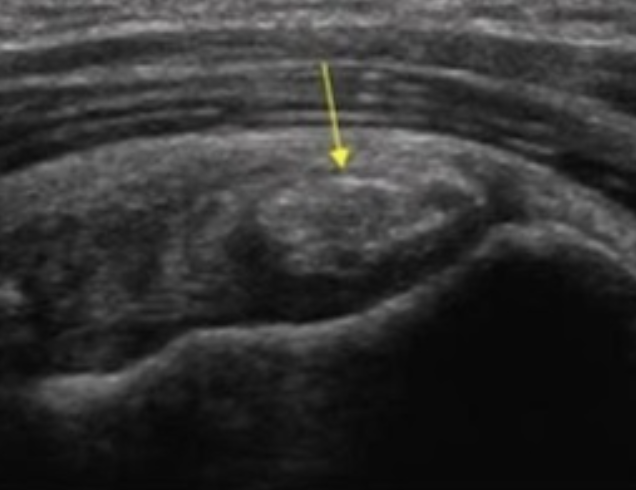

칼슘 성분의 석회가 회전근개 힘줄에 쌓이는 질환으로 결석이나 담석 같은 병처럼 몸 안에 비정상적으로 돌이 생기는 것으로,

회전근개 중 극상근에 가장 많이 생기며 30-60대에 잘 발생합니다.